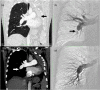

A 46-year-old man 1 year after left-sided pneumonectomy for squamous cell lung cancer presented with severely limited exercise tolerance and dyspnea corresponding to World Health Organization functional class IV (WHO Class IV). After right heart catheterization (RHC), mean pulmonary artery pressure (mPAP) was 43 mmHg and pulmonary vascular resistance (PVR) was 10.2 Wood units (WU). Arteriography revealed organized clots located at the proximal level of the right pulmonary artery, leading to a diagnosis of chronic thromboembolic pulmonary hypertension (CTEPH). The CTEPH team disqualified the patient from surgical treatment due to high perioperative risk and referred him for balloon pulmonary angioplasty (BPA) together with pulmonary hypertension-specific pharmacotherapy (sildenafil). The patient underwent a cycle of nine BPA sessions and completed treatment without complications. Follow-up showed sustained hemodynamic improvement in RHC (mPAP 23 mmHg, PVR 2.6 WU), improved physical capacity (WHO Class II), and relief of dyspnea symptoms.